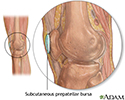

Bursa of the knee - illustration

Bursa of the knee

illustration